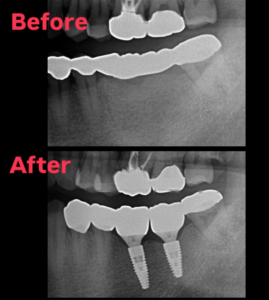

2026.01.04 インプラント ブリッジの不良に対してインプラント治療を行った例 ブリッジの脱離などの不具合を主訴に、インプラントによる咬合治療を行いました。3年程度経過しましたが、経過良好です。 #松本市歯科医院#松本市歯医者#松本市#歯科#歯医者#歯科医院 #根管治療#歯の矯正#精密根管治療#マイクロスコープ#ラバーダム#インプラント#矯正#マウスピース#小児歯科#親知らず#小児矯正#プレオルソ#セラミック#ジルコニア#顎関節#嚥下